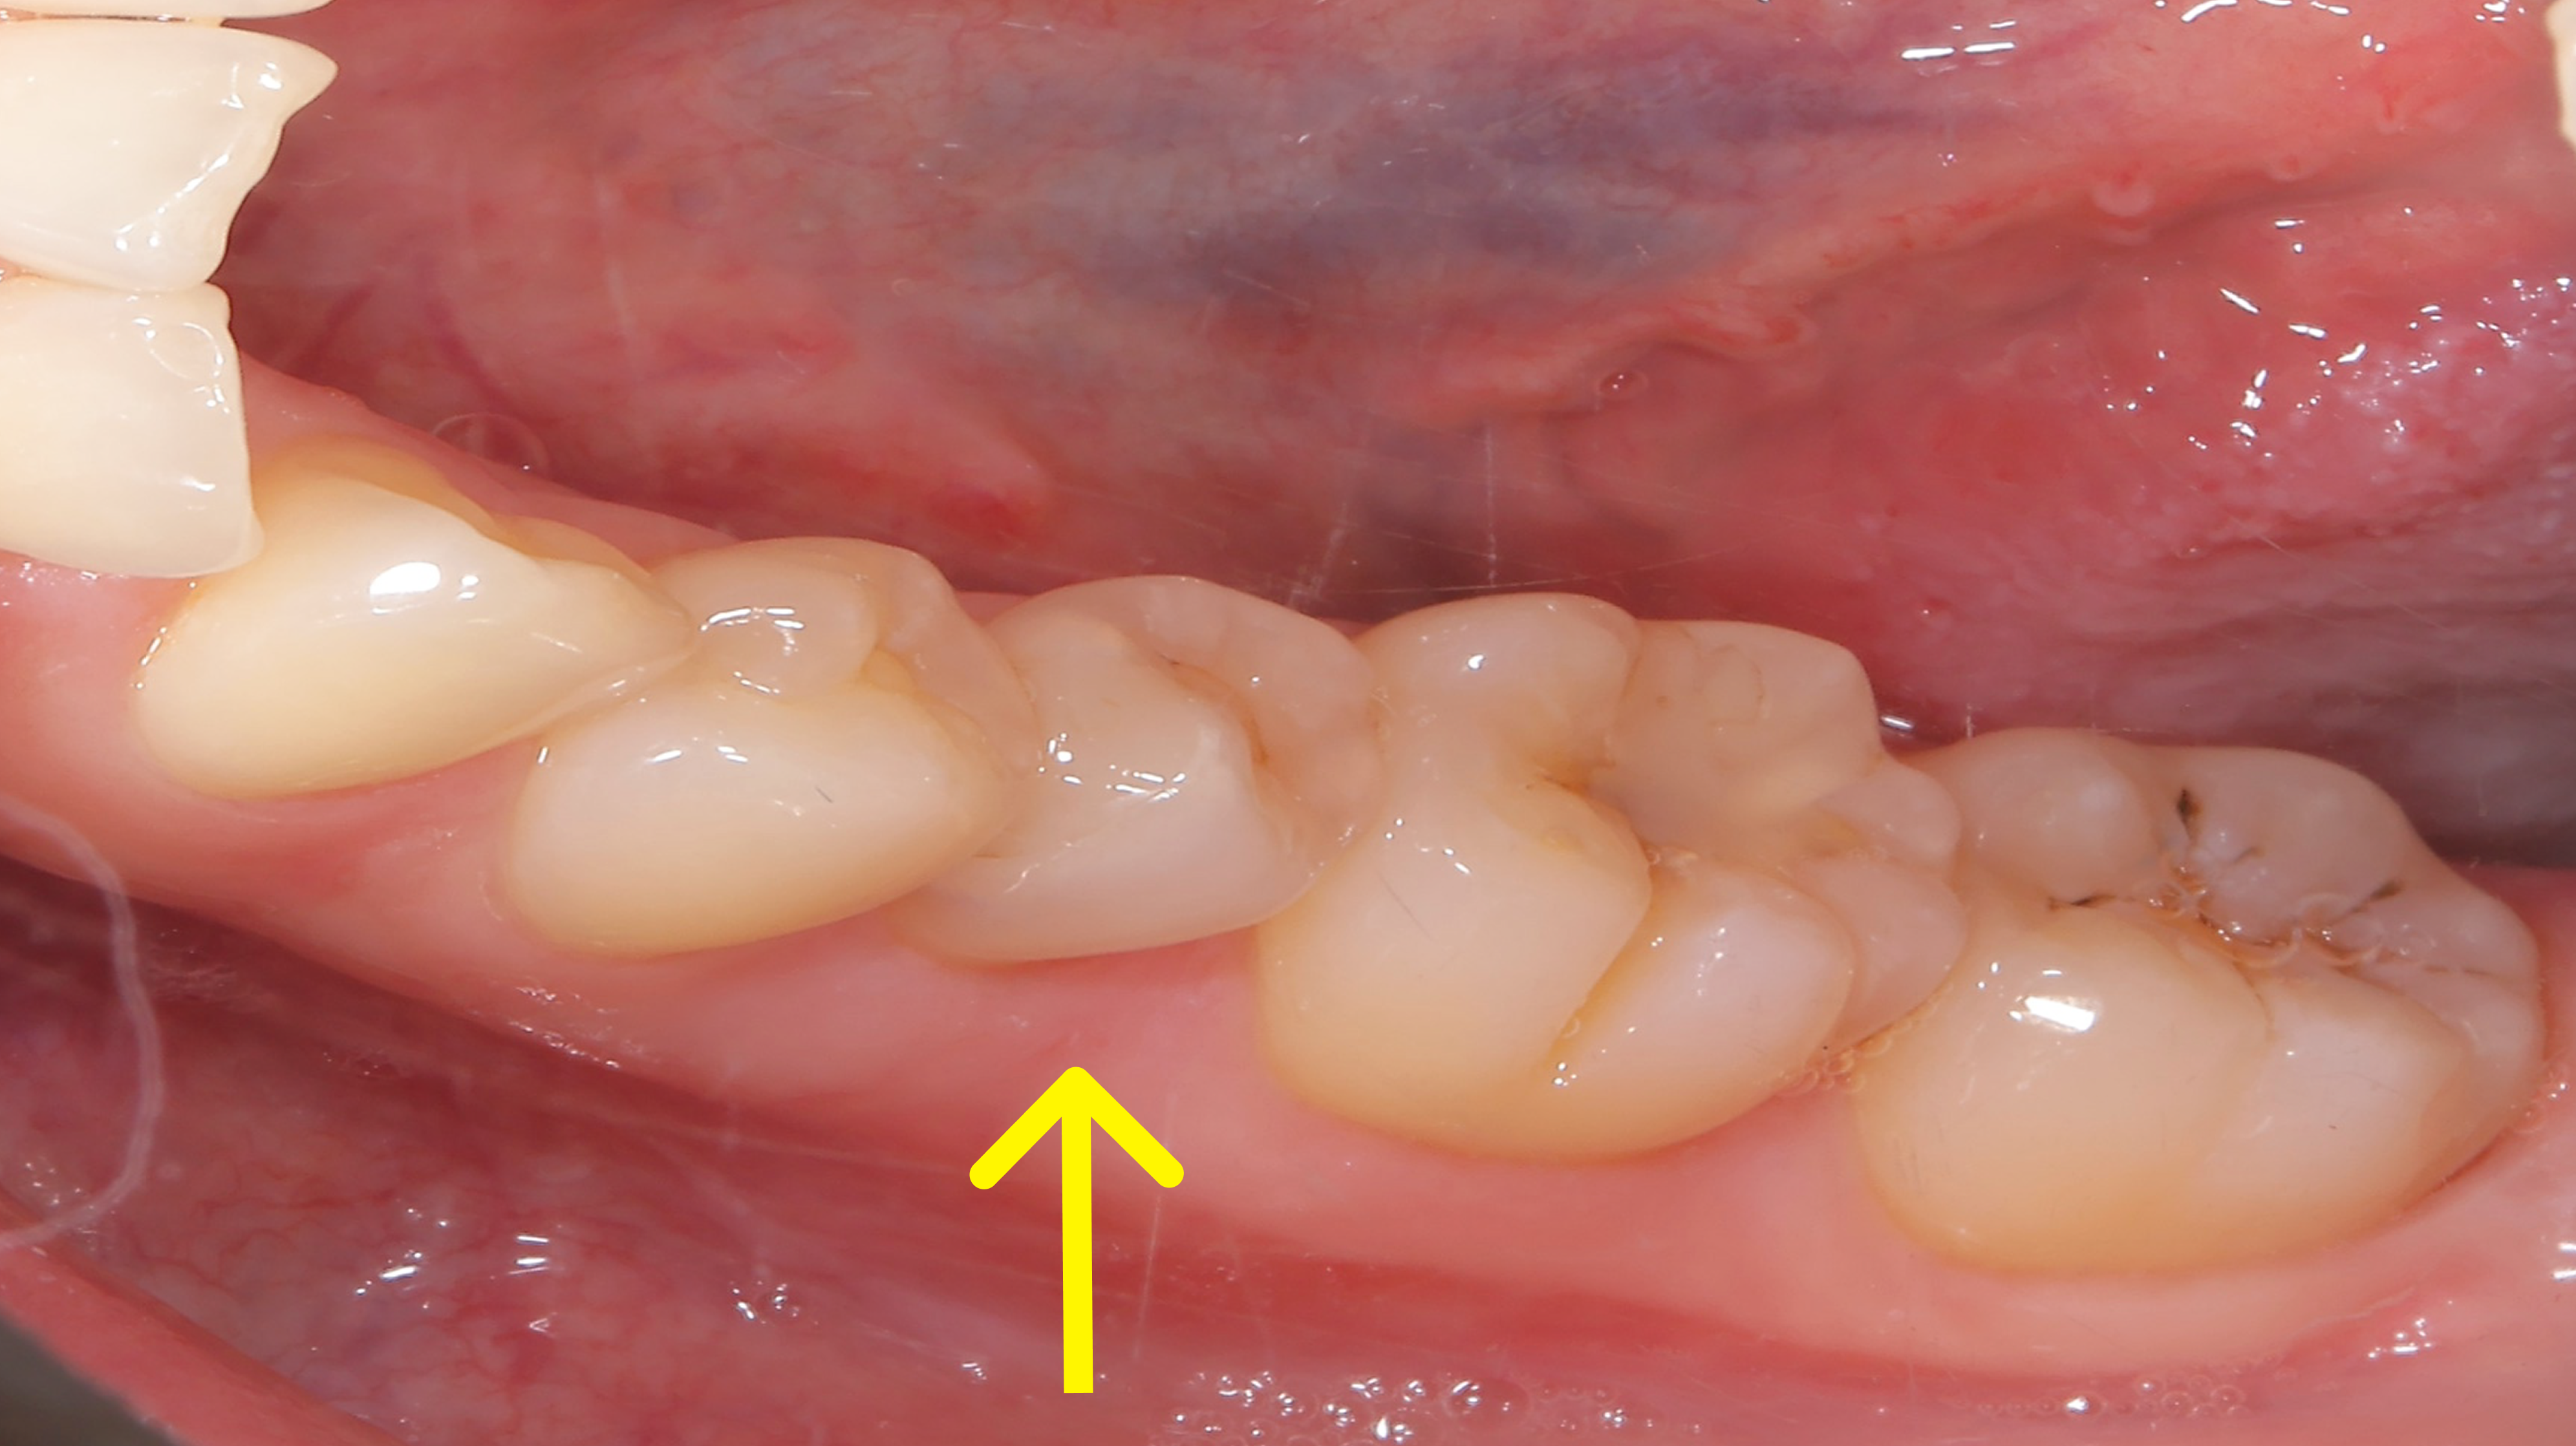

前歯に若干の凸凹はありますが、あとは2期治療で簡単に改善可能です。

治療前

治療後

行った治療

ほぼ他の歯が並んだ状態でも、やはりこの矢印の歯だけ動きが悪かったのと、左下の捻れた歯がなかなか治らなかったので、ワイヤーを部分的に使用させてもらいました。

下の写真が術前術後の比較です。下の前歯が見えるようになりました。上の前歯の傾きが変わるだけで口元の印象も変化します。